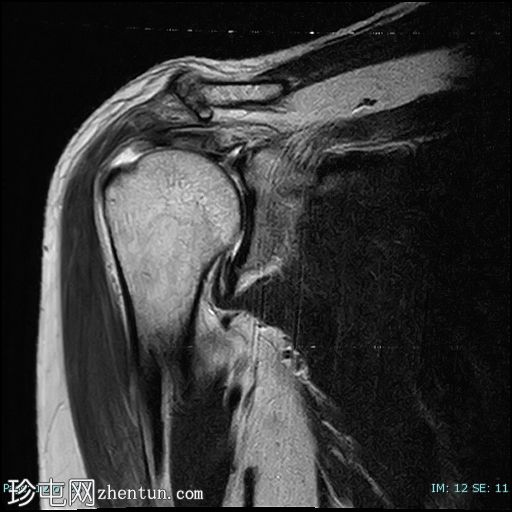

冠状位

T2

冈上肌腱前部纤维及肌腱止点-关键区交界处全层撕裂。撕裂间隙被T2/PD高信号液体填充。肌腱回缩2.1厘米,位于肩峰水平。

未见肱骨头骨内囊性改变或冈上肌腱神经节/黏液囊肿。

冈上肌腱变薄并伴有肌腱病,冈上肌脂肪变性为2级(Goutallier分级)。

肩胛下肌前外侧纤维肌腱病,无肌腱撕裂。

肩锁关节骨关节炎,伴有骨赘、关节囊增厚、囊性改变、骨髓水肿和关节积液。II型肩峰。无肩峰骨。

肱二头肌长头肌腱位于肱二头肌沟内,位置正常,信号和大小正常,腱鞘积液。鉴别诊断:腱鞘炎。

冈下肌和三角肌脂肪变性1级(Goutallier分级)。

肩肱关节软骨变薄,提示退行性肩肱关节软骨软化症。

肩峰下滑囊炎、三角肌下滑囊炎、喙突下滑囊炎和肩胛下滑囊炎。

本病例展示了退行性冈上肌腱撕裂的典型位置,即肌腱足印和关键区交界处。这与创伤性撕裂(通常发生在肌腱交界处)形成对比。

应注意,不应过度依赖质子密度加权成像序列来诊断肩袖撕裂,因为该序列容易出现魔角伪影,从而模拟撕裂。较长的回波时间序列(例如T2加权成像)可以有效避免这种假阳性结果。